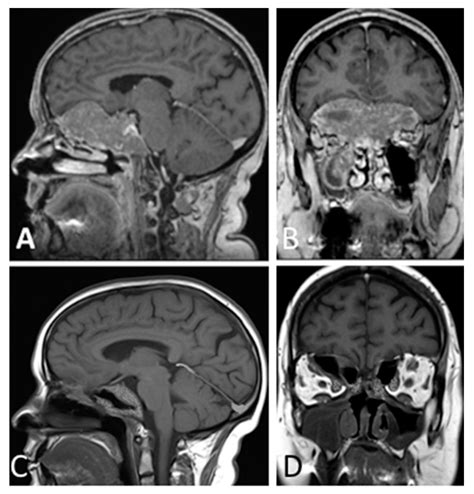

Clival Anomaly Radiology